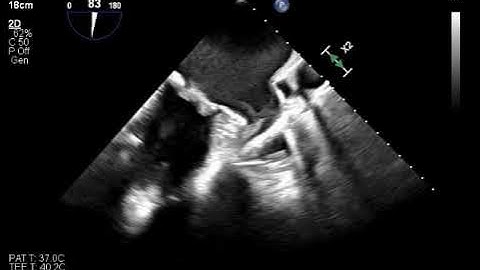

Detection of Left Atrial Appendage Thrombus by TEE